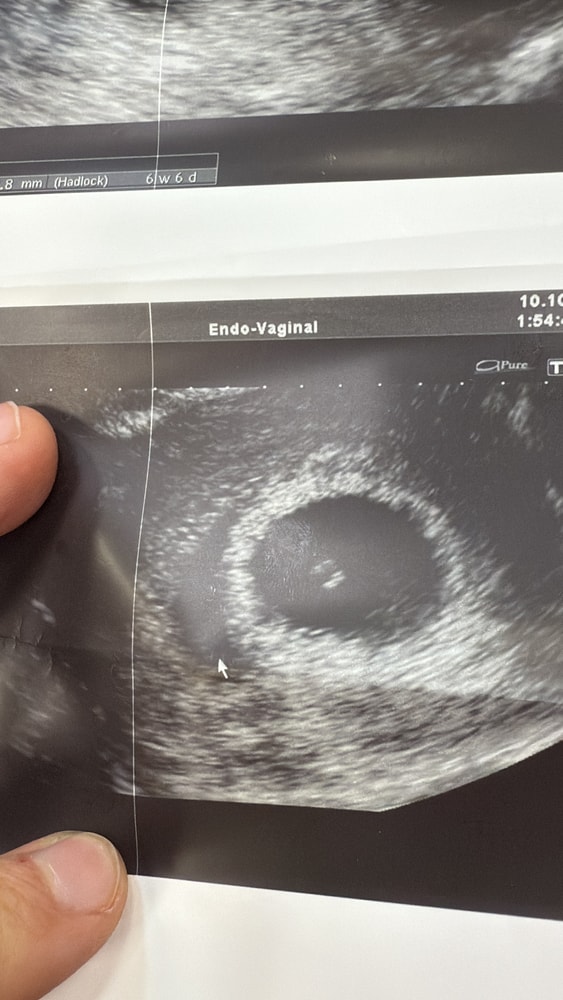

Субхориальная гематома

Изменения и болезни во время БДобрый день .на 6 Нед и 3 дня пошла на узи послушать сердечко и увидеть эмбрион .все это увидела ,но помимо этого написал узист что тонус матки ,субхориальная гематома до 5-6мм, киста желтого 37мм.гинеколог сказала киста ничего страшного ,гематома вроде не больная ,но она длинная и беременность под угрозой.кто сталкивался ?чем закончилась беременность?страшно очень (

Диана, я имела ввиду близко к внутреннему зёву или нет? По фото она тёмная, значит свежая, чем старше гематома тем она светлее на узи. Субамниотическая гематома это ретрохориальная которая пытается организоваться, но её минус в том, что по площади она больше хотя по ширине меньше. Если она у вас близко к внутреннему зёву то нужна госпитализация ибо она может спровоцироваться любым неудачным «пуком» если она по задней стенке. Если по передней то полный мочевой тоже вредно. Ну и плюс она может в любой момент решить опорожниться и потянуть за собой новую кровь. Я вот сейчас с такой гематомой лежу в стационаре, была ретрохориальная, стала такая. 49ммх1,7мм мне сказали что я просто до дома могу не доехать, хотя у меня ничего не кровит и не болит. Назначили много таблеток которые пью

Диана, ой, у вас субхориальная) но в целом рекомендации те же, у моей соседки по палате она самая. Кровотечение открывалось уже несколько раз, благо, что она тут была, а не дома🤷♀️ у неё она как раз по передней стенке. Ну и опасность ретрохориальной в том, что когда она решит опорожниться и возможно потянет «свежую кровь» то это значит, что отслойка хориона станет больше, т.е. нужен постоянный контроль узи